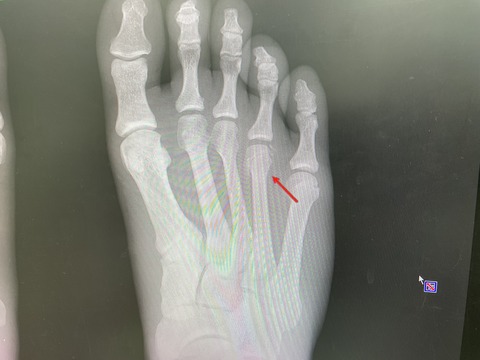

某高校アスリート なんと

今年8月に 世界選手権優勝! 世界 1 獲得!

もちろん、日本選手権優勝!

全日本ランキング1位

国体は間に合わないけれど、アジア選手権は狙っていきます!